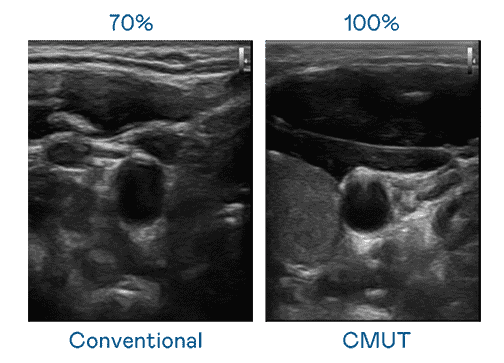

CMUT 技术是一种用电容式微机电元件来产生超音波讯号的技术。。。与传统 PZT 压电式技术相比,,,,CMUT 频宽增加 30%,,,更宽频的超音波讯号让影像解析度大幅提升,,,,是实现高影像品质医疗超音波扫描、、、促进精准医疗发展的关键技术。。

大频宽带来超清晰影像

超音波影像的解析度高低,,,首先取决于探头能发出的讯号频宽。。。银河集团 CMUT 可提供高清晰的超音波讯号,,提供高频宽、、、、高灵敏度、、、、影像纹理细节更高的超音波影像,,,,协助医护人员缩短影像判读时间及利用精准的医疗影像进行诊断。。。。